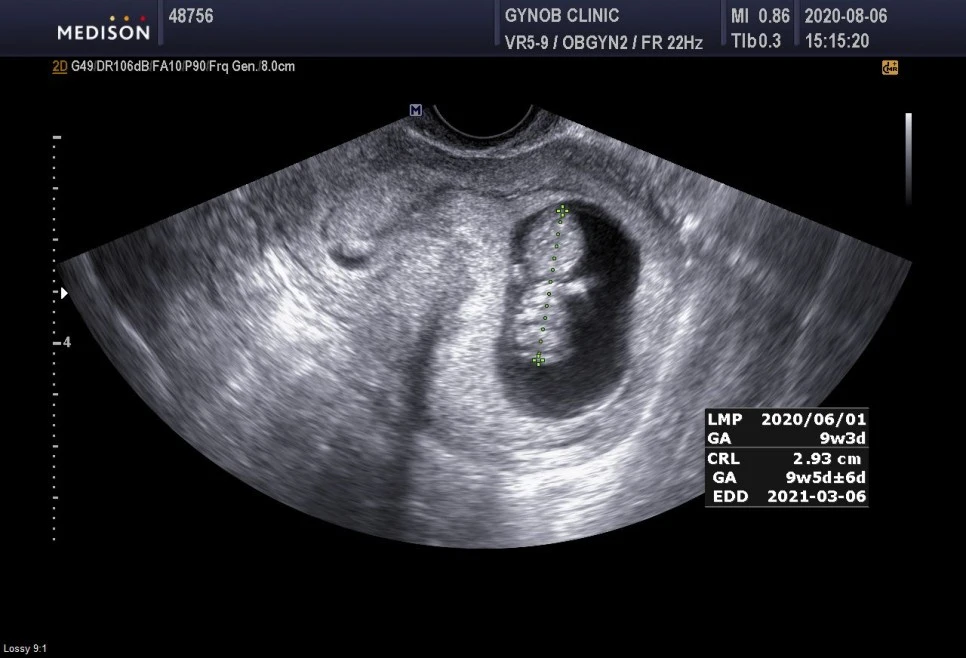

9주차 3일의 초음파 기록.

이제 정말 사람 모양을 하기 시작했다. 진짜 아가처럼 꼬물꼬물 움직이는 모습이 참 신기하다. 주수로는 9주차 3일인데 아가의 상태로는 9주차 5일로 나왔다. 임신 전 내 몸상태며, 피고임에 너무 조심하며 지쳐있던 나와는 다르게 무척이나 잘 커주고 있는 아가를 보니 마음이 한결 더 놓이긴 한다. 이제야 유산스트레스에서 조금은 멀어진 기분이다. 심장박동은 지난주 171에서 166으로 조금 떨어지긴 했으나 아직도 빠른 상태다. 산모가 열이나거나 하는 문제가 아니라면 그렇게 심각한 것은 아니라고.. 의사선생님께서 체온을 물어보시길래 열이 나는 건 아니지만 속 쓰림이 좀 심하다고 말씀드렸는데, 그건 심장이랑 전혀 상관없는 문제라고 내 입덧에 관해서는 1도 관심이 없으신것 같았다. 산모의 흔한 상태인듯ㅠㅜ